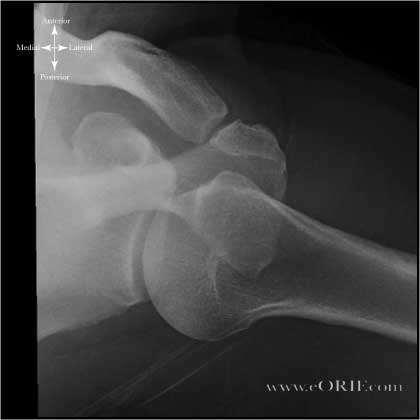

shoulder axillary xray

Normal shoulder axillary view xray.

shoulder axillary arthritis xray

Arthritic shoulder axillary view xray.